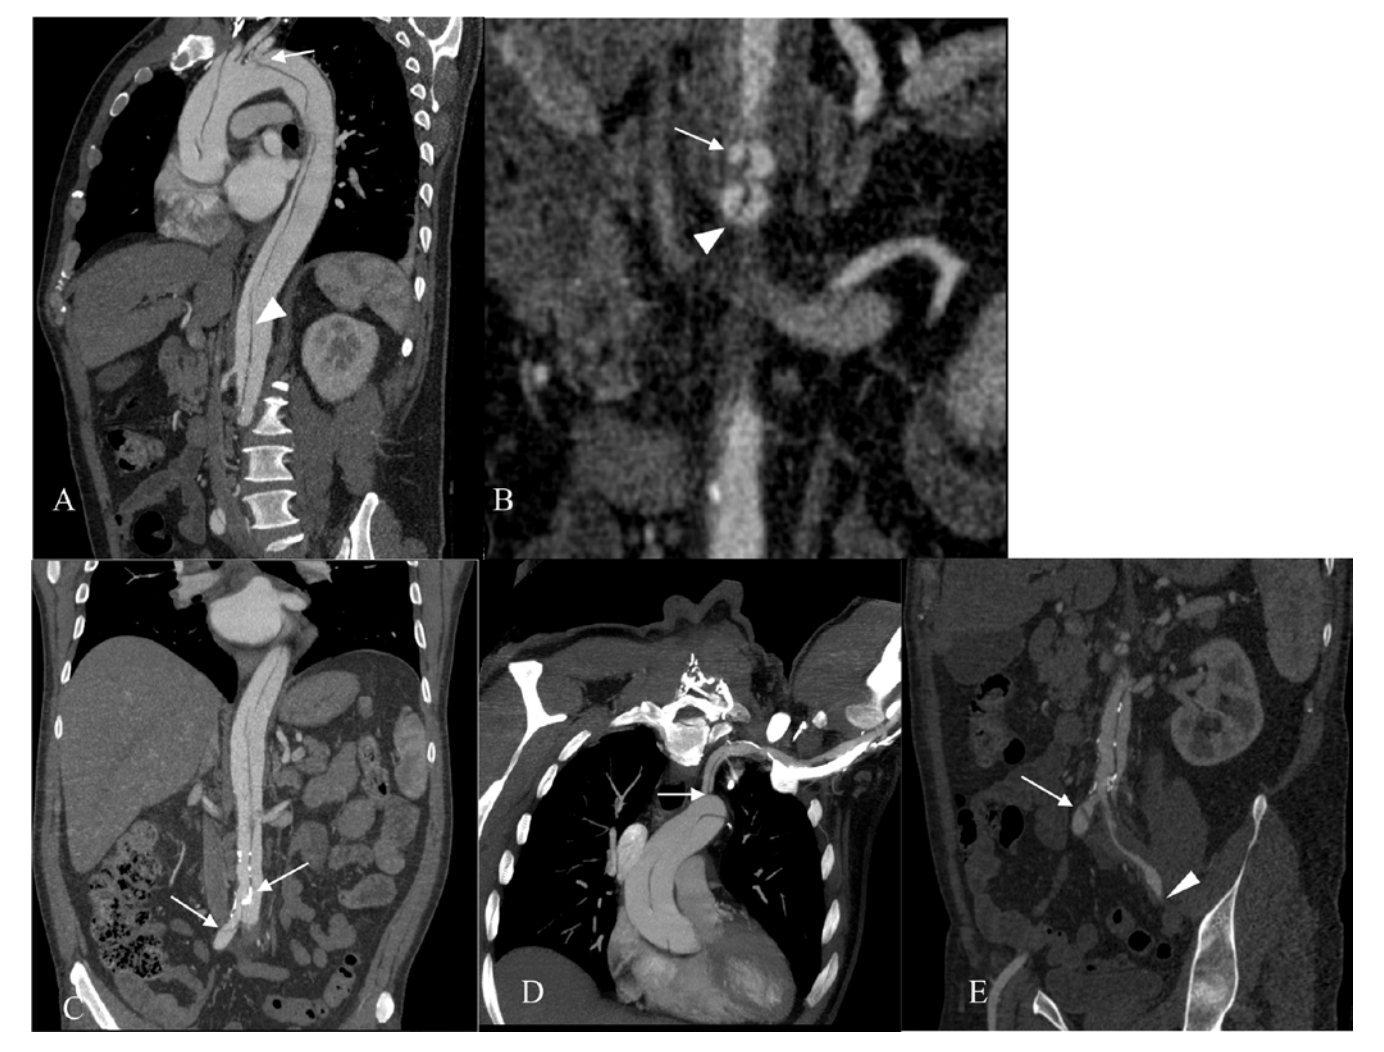

Coronary angiography (CA) was performed 24 hours after admission, an intermediate stenosis was found in the left anterior descending artery (LAD) with TIMI 3 flow (Figure 2). Ventriculography showed mild anteroseptal hypokinesia with a 60% left ventricular ejection fraction (LVEF). Aortic root dilation was observed along with a double contour image suggestive of aortic dissection (Figure 3). Aortic CT was then performed, the study revealed an aortic dissection extending through the thoracic, abdominal and common iliac arteries, classified as a Type A aortic dissection (Figures 4-6). CT angiography 3D reconstruction showed a dissection originating at the aortic root that involved the innominate, left subclavian and left vertebral arteries as well as the descending aorta and extended through the entire course of the common iliac artery causing left iliac artery occlusion (Figure 7).